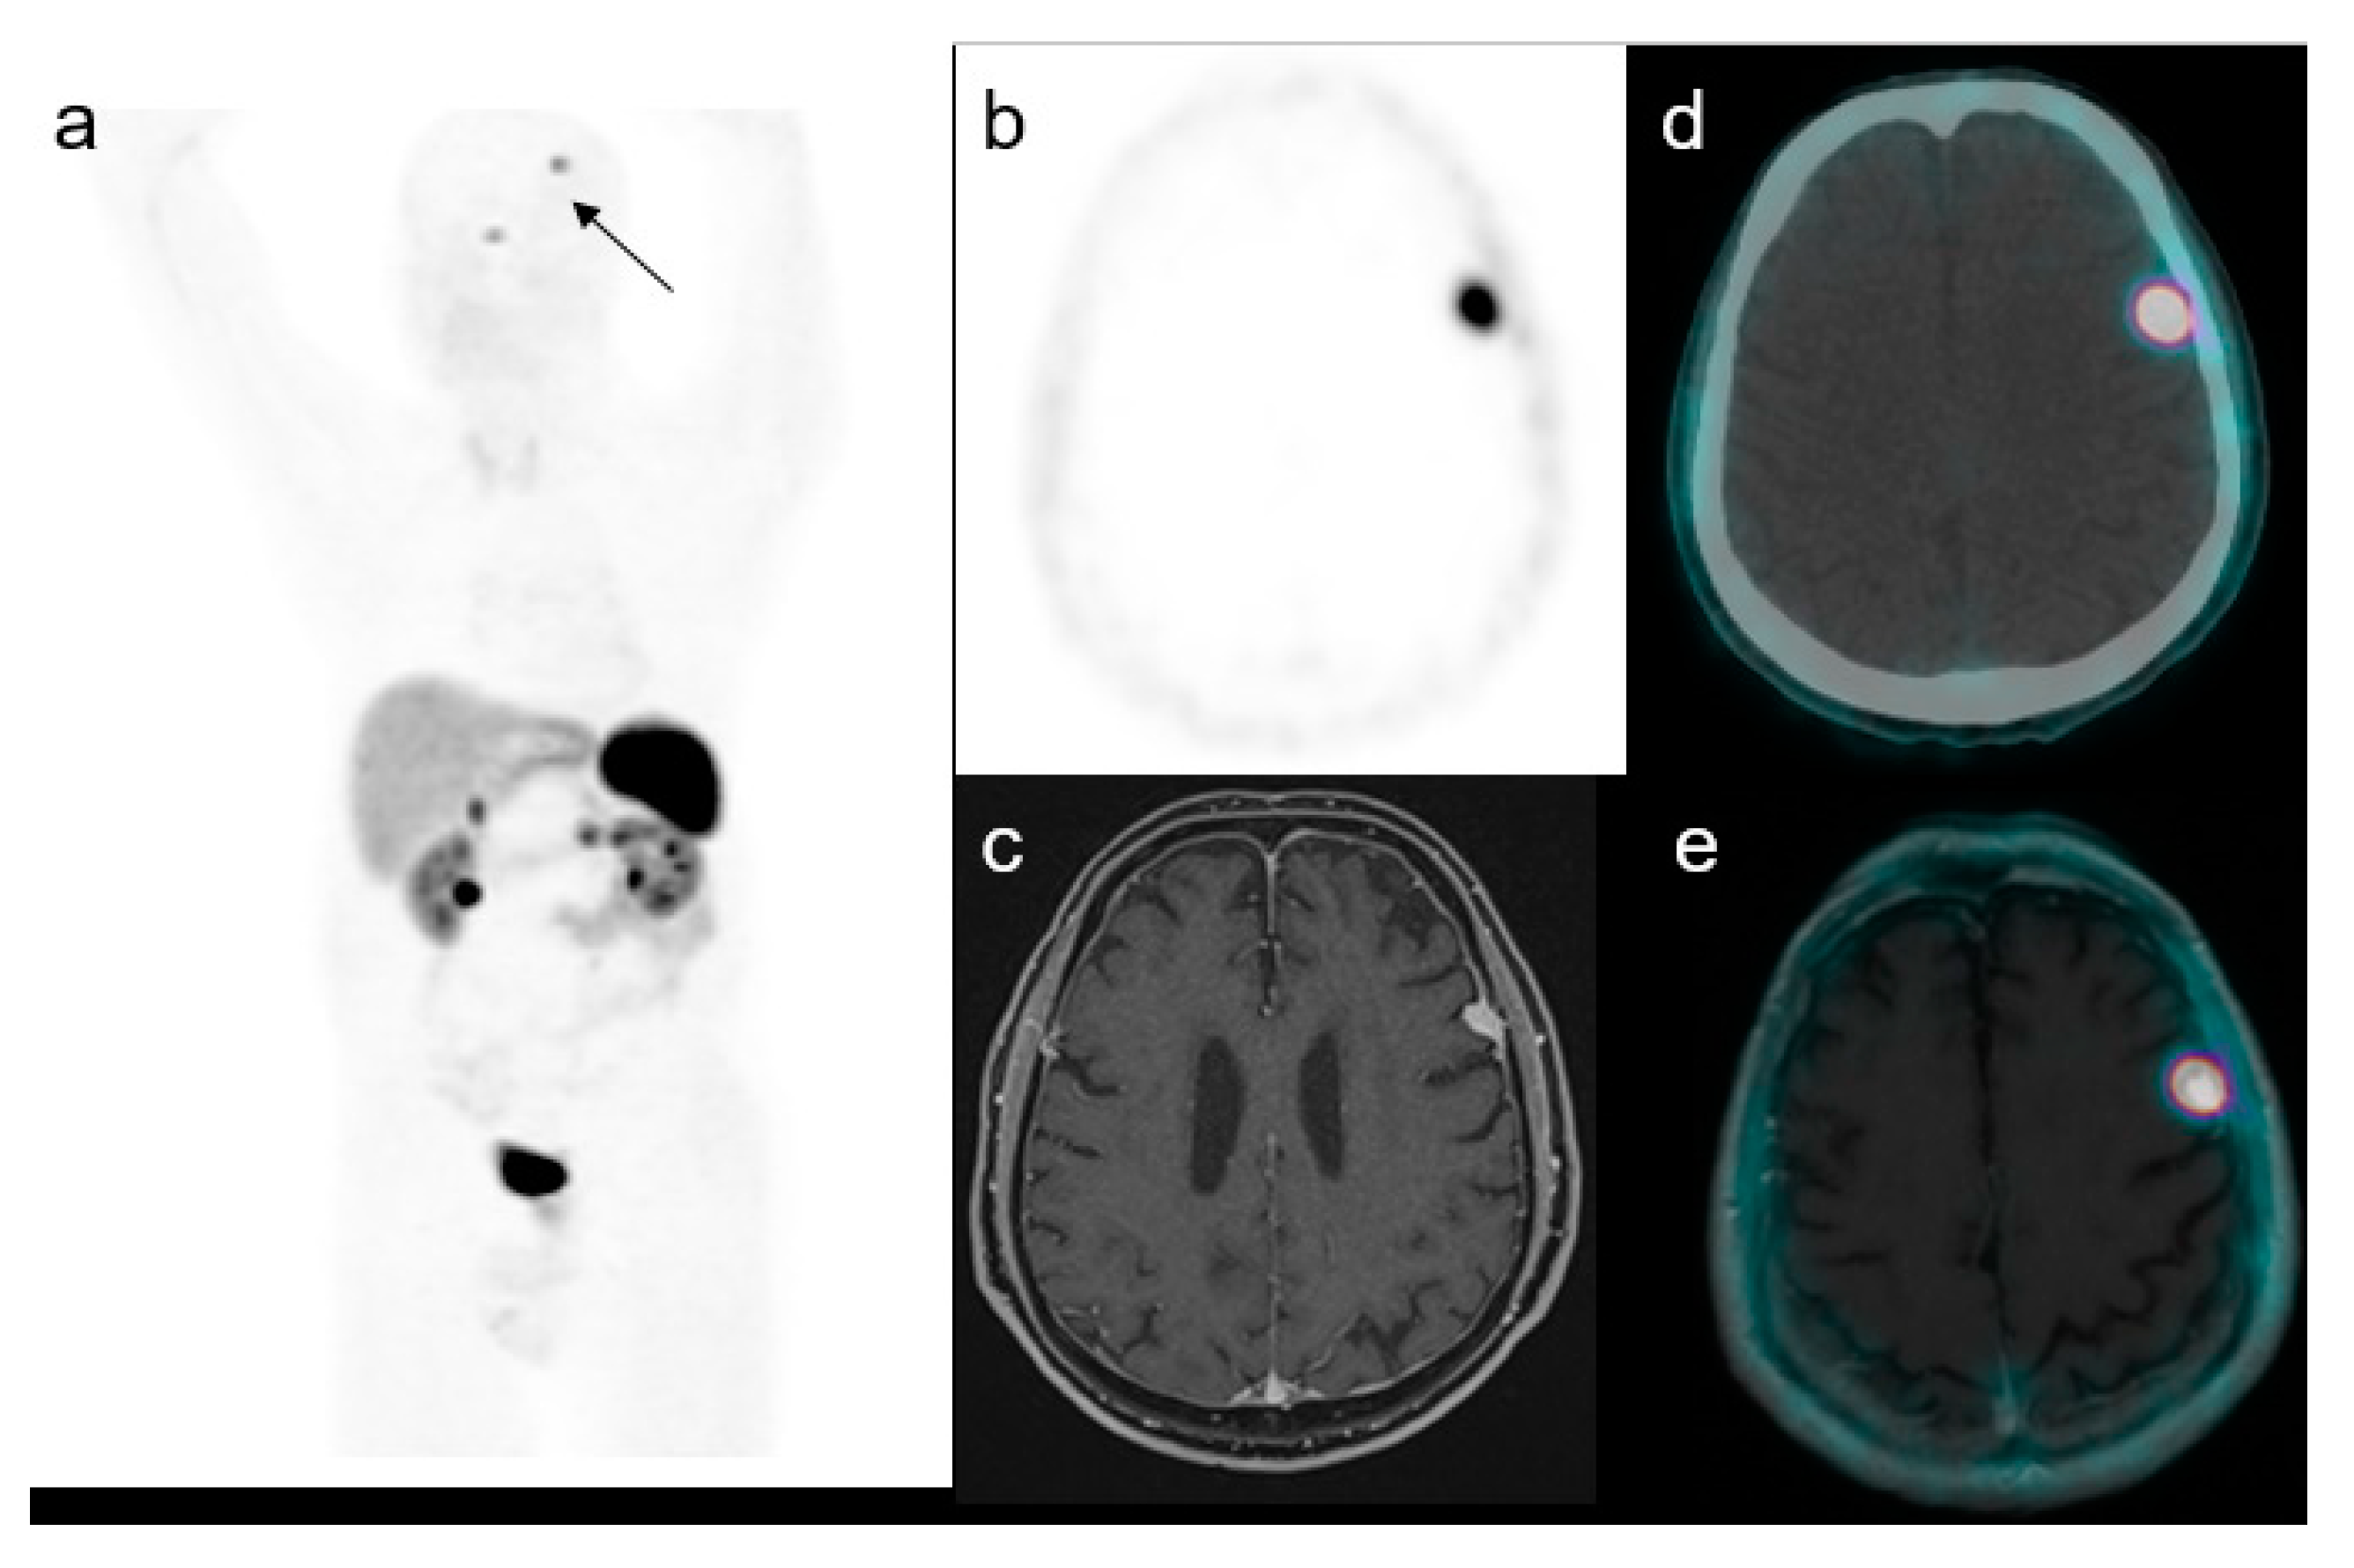

| Lesion size (mm) | 15 ± 6 (7–30) | |

| Multifocal brain uptakes | 4 (11%) | |

| Location | ||

| Right frontal region | 9 (21%) | |

| Left frontal region | 7 (17%) | |

| Right temporal region | 6 (15%) | |

| Left temporal region | 7 (17%) | |

| Right parietal region | 5 (12%) | |

| Left parietal region | 5 (12%) | |

| Left cerebellum | 1 (2%) | |

| Right cerebellum | 1 (2%) | |

| Left parasellar region | 1 (2%) | |

| SUVmax | 16.5 ± 3.7 (5–33) | |

| Lesion to brain SUVmax ratio | 351 ± 198 (80–550) |